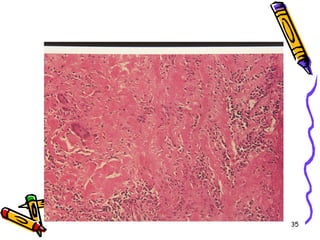

Mikroskopi

• Lezyonlar keskin sınırlı ve segmentaldir

• Fibrinoid nekrozla birlikte lökositik

inflamasyon ve tromboz

• İnflamasyon nedeni ile duvarda zayıflama

ve anevrizmal dilatasyon

• Damarın beslediği dokularda infarktüs,

atrofi, hemoraji